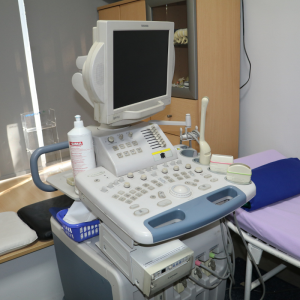

Uz pomoć najsavremenije tehnologije kao što je 4D ultrazvuk, ali i zbog velikog stručnog znanja, naši doktori brzo i precizno rade prevenciju, dijagnostiku i samo liječenje pacijenata.

Savremeni aparati

U udobnom prostoru, opremljenom savremenim aparatima, pacijentima pružamo visokostručnu medicinsku uslugu, maksimalan komfor i diskreciju

Kod nas možete dobiti kompletnu ginekološku njega koja uključuje: ginekološke preglede, ginekološki ultrazvuk. ekspertni ultrazvuk, 3D i 4D ultrazvuk, loop ekcizija, kolposkopiju, PAPA test, CTG, radiotalasno uklanjanje kondiloma, konsultacije za IVF, folikulometriju...